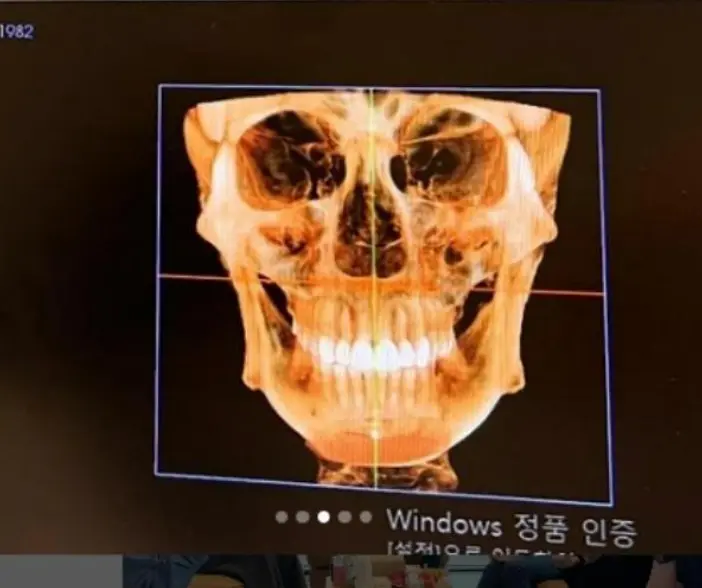

Ancak ünlü modelin X-Ray cihazından geçerken alarm vermesinin sebebinin çenesine yerleştirilen implantlardan kaynaklı olduğunu düşünmüş, çenesindeki protezlerin çivilerinin röntgende burnunda ve kafasının çeşitli yerlerinde olduğunu belirtti.

Güvenlik görevlileri kadının X-Ray'den geçmesine izin verirken genç kadın, implantların kafatasına doğru yürüfüğünü iddia etti.

Milliyet Pembe Nar'da yer alan habere göre ise, Diş Doktoru Murat L Mercan, "Diş implantları, eksik dişlerin yerine koyulan ve çene kemiğine yerleştirilen titanyum vidalardır. Bu vidalar, çene kemiği ile bütünleşerek sağlam kaynaşmış bir yapı oluşturur ve üzerine protez diş yerleştirilir. İmplantların, uygun şekilde yerleştirildiğinde yerlerinden kayması veya vücudun başka bölgelerine hareket etmesi neredeyse imkansızdır. Haberdeki vidalar, estetik ameliyatlar sırasında konulan vidalar olup diş implantlarıyla hiçbir ilgisi yoktur" dedi.

Diş İmplantlarının titanyumdan yapıldığı küçük boyutlarıyla X-Ray cihasınd herhangi bir alarm vermeyeceğini belirten Diş Doktoru Mercan, ''Nadir durumlarda çok sayıda implant veya büyük metal protezler tarayıcılarda algılanabilir" dedi.

Tayvanlı ünlü model Fang'ın ise estetik operasyonlar neticesinde yüz cerrahisinde kullanılan vidaların olabileceği öğrenildi.